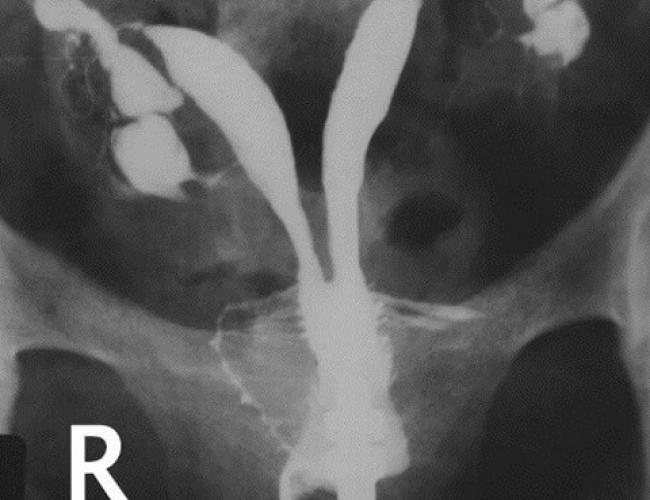

Kadınlarda sağlı solu iki adet tüp bulunmaktadır. Tüplerle ilgili herhangi bir sorun tespit edilirse hastanın tüp bebek yaptırması gerekebilir.

Çocuk sahibi olmak isteyen çiftlerin ortalama %15-20 ‘ sinde kısırlık – infertilite sorunu ile karşılaşmaktayız. Bunlarında % 40-50 sinde erkeğe bağlı sorunlardan dolayı...